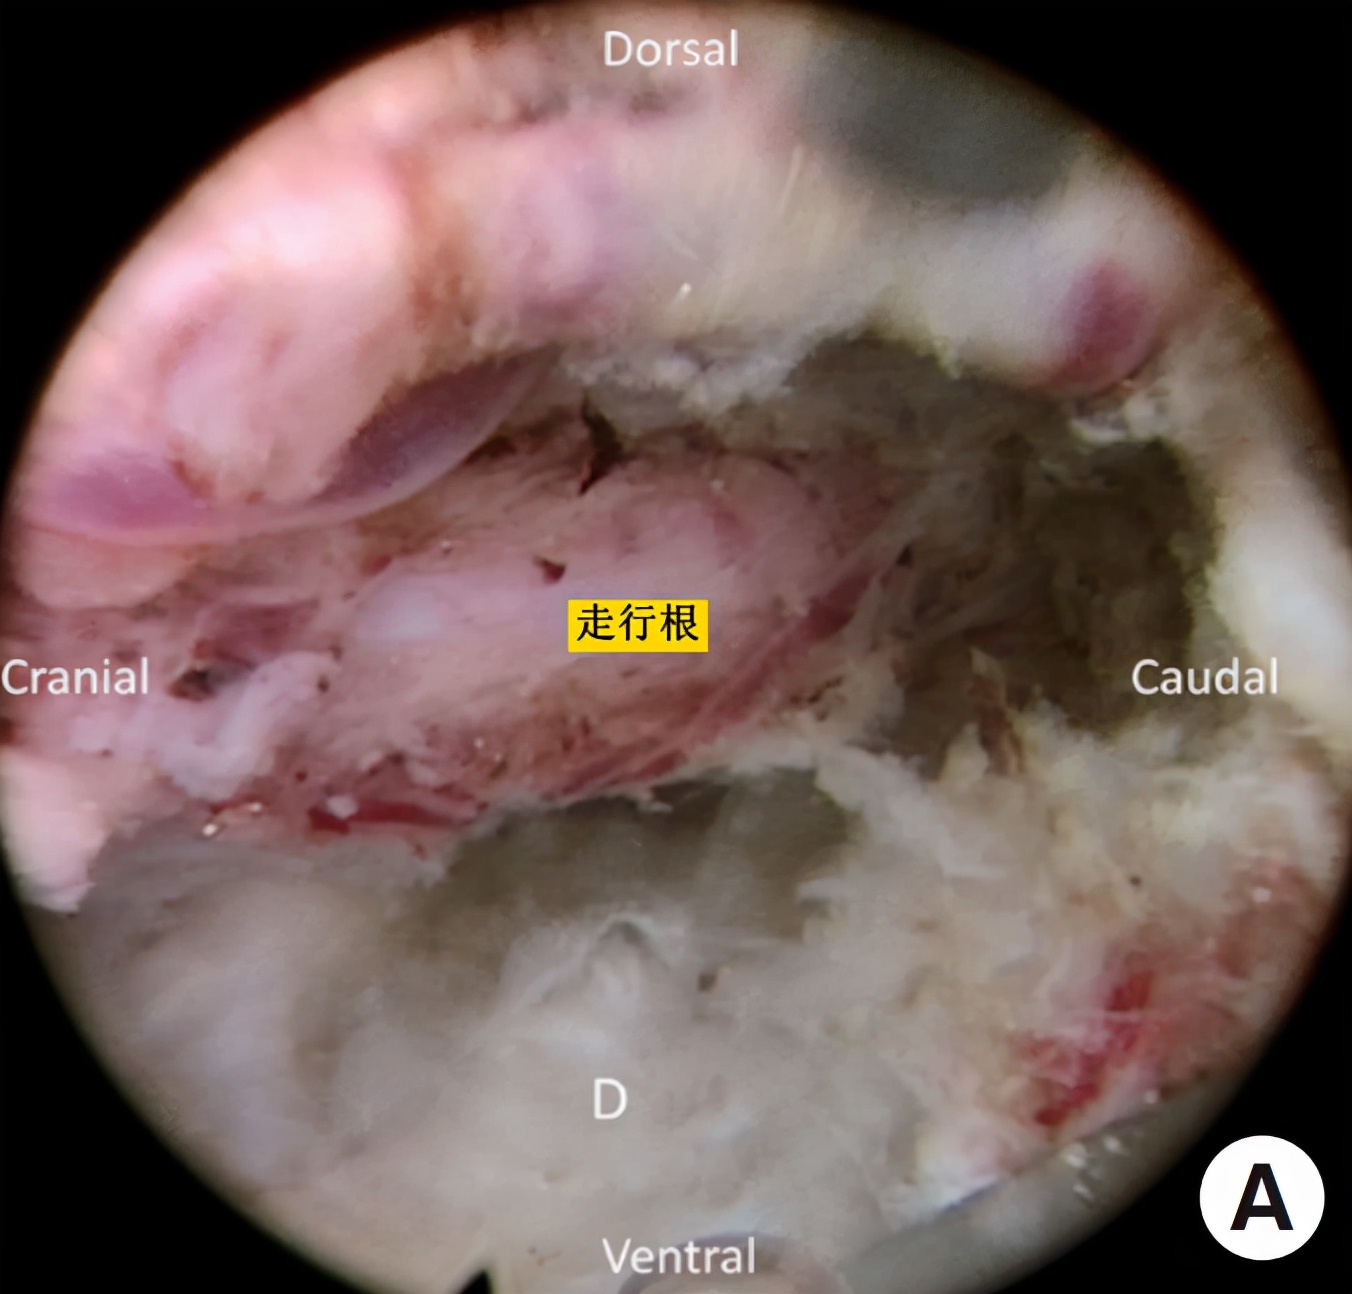

图4:(A)椎间孔成形术后显露突出的椎间盘(B)椎间盘切除术后显露走行根。

☆检查出血、可能残余的椎间盘和神经根;神经根的边缘自由和良好搏动表示充分减压。

图5:(A)减压侧隐窝及走行根(B)撤回内镜,将视野向头侧旋转,显示出口根,以确认充分的减压。